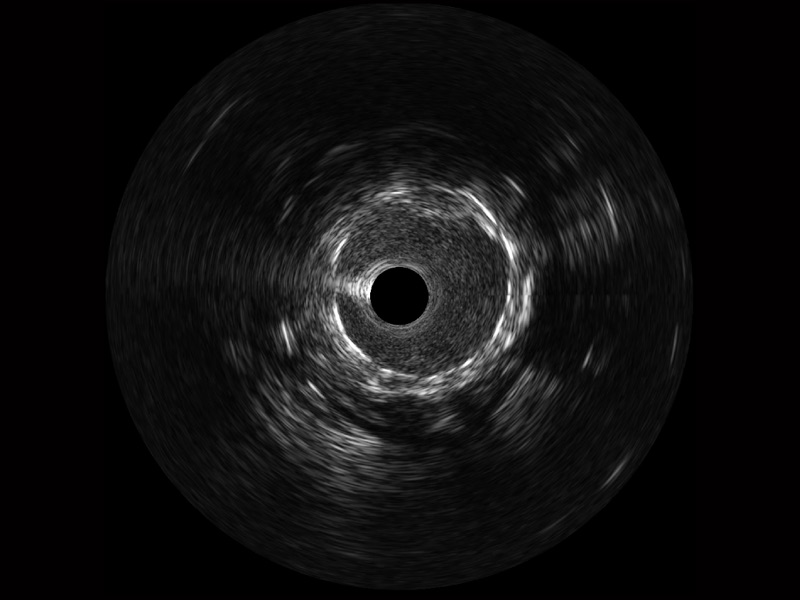

開立寬頻IVUS圖像

傳統(tǒng)IVUS圖像

對比傳統(tǒng)IVUS導管成像,開立寬頻IVUS圖像的近場支架梁顯影更細膩,遠場中膜外血管仍清晰可辨,兼顧遠中近,兼顧分辨力與穿透深度